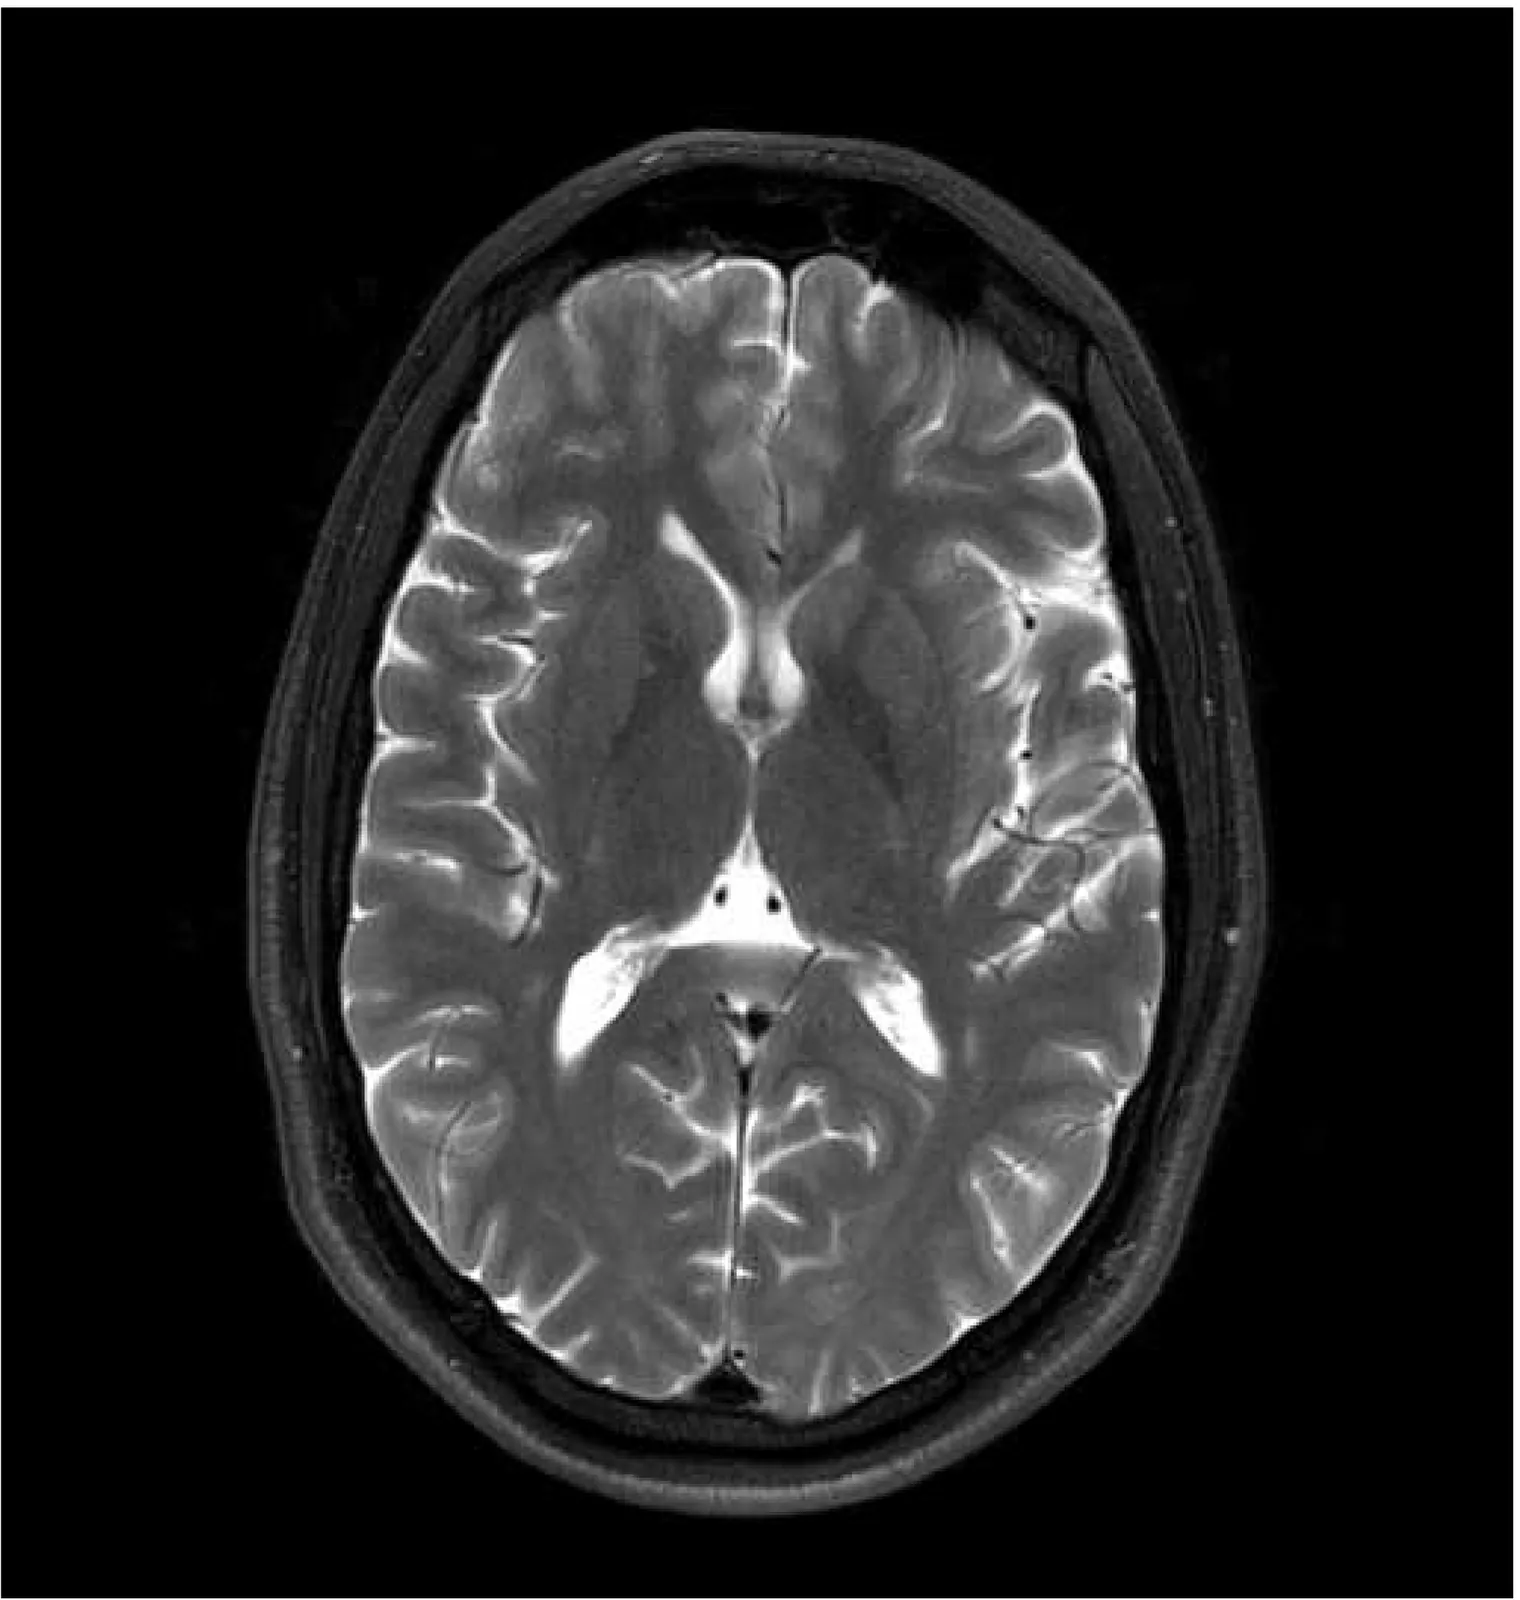

Magnetic resonance imaging (MRI) is a cornerstone of clinical neuroimaging, yet conventional MRIs provide qualitative information heavily dependent on scanner hardware and acquisition settings. While quantitative MRI (qMRI) offers intrinsic tissue parameters, the requirement for specialized acquisition protocols and reconstruction algorithms restricts its availability and impedes large-scale biomarker research. This study presents a self-supervised physics-guided deep learning framework to infer quantitative T1, T2, and proton-density (PD) maps directly from widely available clinical conventional T1-weighted, T2-weighted, and FLAIR MRIs. The framework was trained and evaluated on a large-scale, clinically heterogeneous dataset comprising 4,121 scan sessions acquired at our institution over six years on four different 3 T MRI scanner systems, capturing real-world clinical variability. The framework integrates Bloch-based signal models directly into the training objective. Across more than 600 test sessions, the generated maps exhibited white matter and gray matter values consistent with literature ranges. Additionally, the generated maps showed invariance to scanner hardware and acquisition protocol groups, with inter-group coefficients of variation $\leq$ 1.1%. Subject-specific analyses demonstrated excellent voxel-wise reproducibility across scanner systems and sequence parameters, with Pearson $r$ and concordance correlation coefficients exceeding 0.82 for T1 and T2. Mean relative voxel-wise differences were low across all quantitative parameters, especially for T2 ($<$ 6%). These results indicate that the proposed framework can robustly transform diverse clinical conventional MRI data into quantitative maps, potentially paving the way for large-scale quantitative biomarker research.

The 3D fast silent multi-parametric mapping sequence with zero echo time (MuPa-ZTE) is a novel quantitative MRI (qMRI) acquisition that enables nearly silent scanning by using a 3D phyllotaxis sampling scheme. MuPa-ZTE improves patient comfort and motion robustness, and generates quantitative maps of T1, T2, and proton density using the acquired weighted image series. In this work, we propose a diffusion model-based qMRI mapping method that leverages both a deep generative model and physics-based data consistency to further improve the mapping performance. Furthermore, our method enables additional acquisition acceleration, allowing high-quality qMRI mapping from a fourfold-accelerated MuPa-ZTE scan (approximately 1 minute). Specifically, we trained a denoising diffusion probabilistic model (DDPM) to map MuPa-ZTE image series to qMRI maps, and we incorporated the MuPa-ZTE forward signal model as an explicit data consistency (DC) constraint during inference. We compared our mapping method against a baseline dictionary matching approach and a purely data-driven diffusion model. The diffusion models were trained entirely on synthetic data generated from digital brain phantoms, eliminating the need for large real-scan datasets. We evaluated on synthetic data, a NISM/ISMRM phantom, healthy volunteers, and a patient with brain metastases. The results demonstrated that our method produces 3D qMRI maps with high accuracy, reduced noise and better preservation of structural details. Notably, it generalised well to real scans despite training on synthetic data alone. The combination of the MuPa-ZTE acquisition and our physics-informed diffusion model is termed q3-MuPa, a quick, quiet, and quantitative multi-parametric mapping framework, and our findings highlight its strong clinical potential.